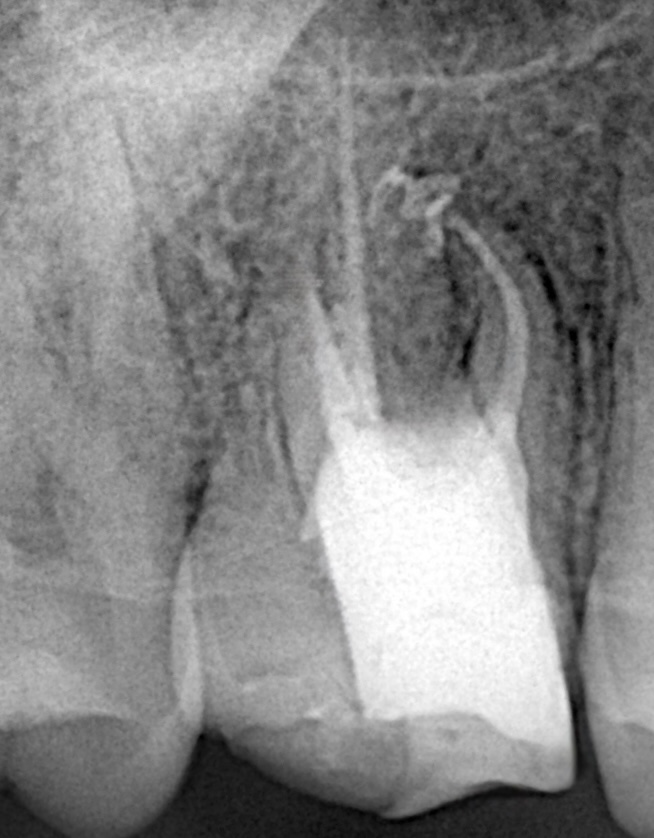

The tooth was isolated with a heavy-gauge rubber dam. Conservative access refinement under 16× magnification preserved pericervical dentin while improving canal visualization. (Fig 1)

Fig 1: Access refinement and canal scouting under microscope isolation.